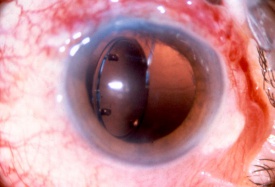

Refractive lens exchange and cataract surgery remove the crystalline lens and replace it with an IOL. Prior to the phacoemulsification era, extracapsular cataract (ECCE) surgery involved a large limbal incision or scleral tunnel. While ECCE incisions were historically as large as 10 mm in chord length, phacoemulsification cataract surgery employs a clear corneal incision (or narrow scleral tunnels), which typically ranges between 2.2 to 2.75 mm. Phakic IOLs (pIOL) are able to correct ametropia by lens insertion into 3 anatomical locations: anterior chamber iris fixated (Artisan/Verisyse), anterior chamber angle supported (Kelman Duet, Acrysof Cachet), or posterior chamber with no fixation (Implantable Collamer Lenses).[38][39] Incisions from these surgeries produce a potential area of weakness that may lead to wound dehiscence after trauma. Larger incisions from traditional ECCE are more likely to suffer dehiscence than smaller phacoemulsification or pIOL incisions.[40][41] Prior cataract surgery may stress the zonular support, and subsequent trauma may dislocate the implanted IOL. Ruptured ECCE wounds account for a significant proportion of all open globe injuries, and they are associated with a high possibility of retinal damage (e.g. choroidal hemorrhages and retinal detachment), often leading to a poor visual outcome. Dehiscence of the phacoemulsification wound is less common and is more frequently associated with a better visual prognosis. Other pathology related to trauma may involve IOL dislocation within the eye from an associated zonulopathy or capsular tear. The IOL may also be partially or completely expelled from globe through a weakened area (i.e. prior incisions).

Although uncommon, traumatic dislocation of pIOLs has been reported. Complete aniridia, with expulsion of the crystalline lens and vitreous through the 6 mm surgical wound has been reported 6 months following Artisan lens implantation (anterior chamber iris fixated).[42] It was hypothesized that the trauma caused the enclavated lens to shear the iris from its root thereby creating a complete iridodialysis, resulting in traumatic aniridia. Partial aniridia has also been reported.[43] Decentration/dislocation of the pIOL is also a potential sequela of trauma. Additionally, cataract formation may occur with pIOLs and is conceivably more common following trauma, especially with posterior chamber positioned pIOL. There is also a risk of endothelial cell damage and resulting corneal decompensation with traumatic IOL dislocations.

There are still a significant number of the pseudophakic elderly individuals, who underwent traditional ECCE. While all incisions should be carefully inspected, a history of ECCE should prompt attentive inspection of the ECCE wound. There should be a low threshold to perform exploration of the globe, in order to exclude a potentially dehisced cataract wound, particularly in the setting of bullous subconjunctival hemorrhage.[40] Fluorescein can be used to check for Seidel test positivity of suspicious wounds. Examination of the IOL or pIOL, after trauma, may require head positioning to identify displacement, dislocation or significant pseudophakodonesis (signs of zonular trauma damage). Slit lamp examination in patients with a history of pIOL implantation must be performed with special attention to the haptic enclavation sites on the mid-peripheral iris for iris-fixated pIOLs and to the haptic position for the other pIOL types. In all cases of trauma, after cataract surgery, the cornea should be examined for edema, which may be suggestive of endothelial cell damage. Intraocular pressure must be measured, and a gonioscopic examination should be performed, if possible, given the patient’s risk of peripheral anterior synechae and potential iridodialysis or cyclodialysis.[44] Pupil irregularity, iris atrophy, iris tears and iris transillumination defects should be noted and may be associated with pupillary ovalization.

An irregular pupil can also be indicative of a dislocated IOL and /or a partially extruded IOL. Iris atrophy (sectoral) or transillumination defects may signify trauma from a dislocated IOL that is now in contact with the iris. The slit beam must also be directed toward the pIOL and natural lens to assess the distance between the posterior surface of the pIOL and the anterior surface of the crystalline lens. pIOL/lens touch following trauma may also be associated with increased risk of cataract formation. The anterior chamber should also be evaluated for hyphema as well as cell and flare.